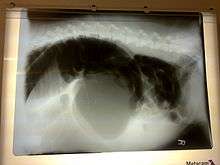

X-ray from the side of a dog with severe intestinal gastric dilatation-volvulus.